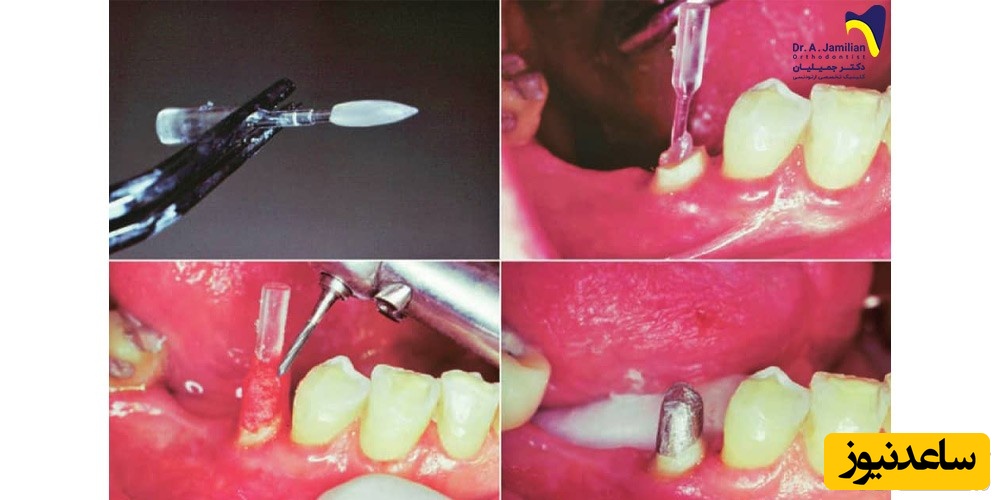

گاهی مواقع نیز می توان دندان را با استفاده از یک پین پر نمود. این در صورتی است که قسمت زیادی از دندان از بین نرفته باشد. به این ترتیب یک پایه فلزی درون ریشه قرار می گیرد تا به حفظ و نگهداری آمالگام یا کامپوزیت در دندان کمک کند.برای ترمیم دندان با پست و کورف در ابتدا باید کمی از دندان را تراشید تا جایی که نسج دندان باقی بماند. سپس از ریشه دندان برای ساخت Post یک قالب تهیه می شود. پست بر اساس این قالب در لابراتوار ساخته می شود.بعد از ساخت پست، آن را داخل با چسبی مخصوص قرار می دهند. سپس یک تاج مصنوعی که به آن کور گفته می شود روی آن قرار می گیرد. در انتها از این دندان یک قالب برای ساخت روکش تهیه می شود. البته در گاهی از مواقع برای قرار گیری قالب روی دندان به یک جراحی ساده نیز نیاز است. در این جراحی کمی از لثه در اطراف دندان برداشته می شود تا قالب دندان به خوبی روی دندان قرار بگیرد. با گذشت زمان لثه بالا آمده و اطراف روکش را احاطه می کند، مانند دیگر دندان های طبیعی.